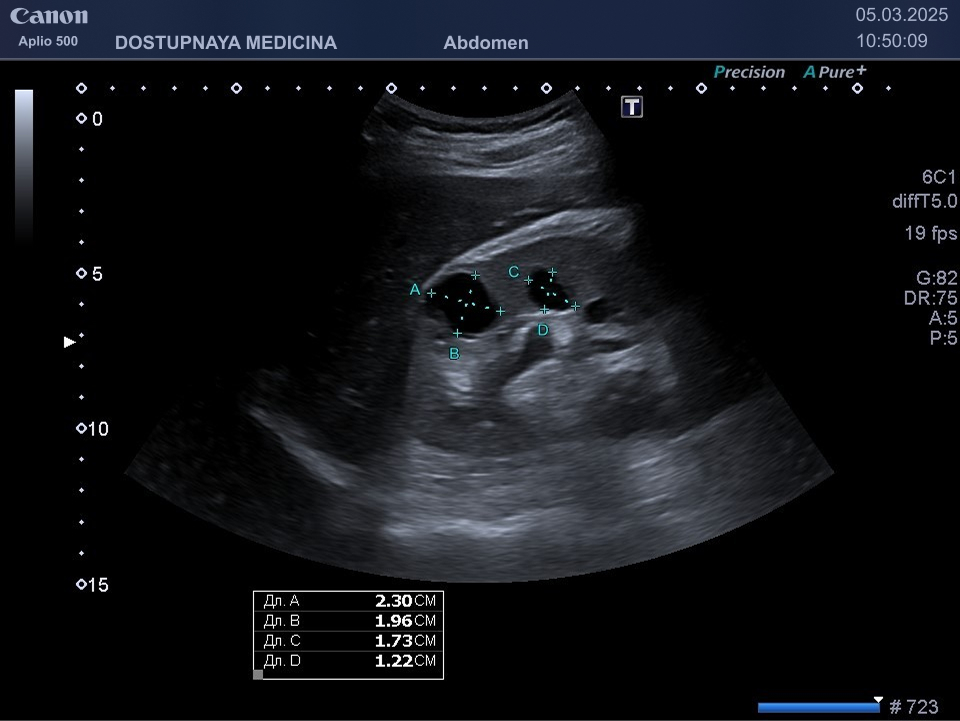

Сонографическими критериями поликистозной болезни почек при наличии этой болезни у родителей следует считать наличие двух и более кист в одной или обеих почках в возрасте меньше 30 лет, наличие двух и более кист в каждой почке в возрасте 30-59 лет и наличие четырёх кист в каждой почке в возрасте 60 лет и более.

Кисты небольших размеров (до 3 см), как правило, не требуют никакого лечения, необходимо лишь контролировать размеры и количество кист не реже 1 раза в 6-12 месяцев. Кисты от 3 до 5 см можно пунктировать и дренировать под контролем УЗИ с последующим введением в них склерозирующего препарата. Более крупные кисты (больше 5 см), как правило, иссекают лапароскопически. Медикаментозного лечения кист на данный момент не существует.

Существует классификация кист Bosniak по степени онкологической опасности:

- Bosniak 1- простая киста с тонкими стенками (до 2 мм) с жидким содержимым, без перегородок и солидного компонента, требует наблюдение 1 раз в полгода.

- Bosniak 2 – киста с перегородками и толщиной стенки 3мм или простая киста больше 3 см, требует наблюдение 1 раз в 2 месяца

- Bosniak 3- мультинодулярные, геморрагические кисты, кисты с крупными кальцинатами и солидным компонентом, требуют оперативного лечения в связи с высоким риском цистаденокарциномы.